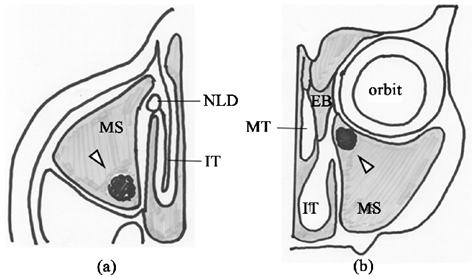

Esquema de uma infecção dentro do seio maxilar, onde é demonstrada a bola fúngica pela seta branca.